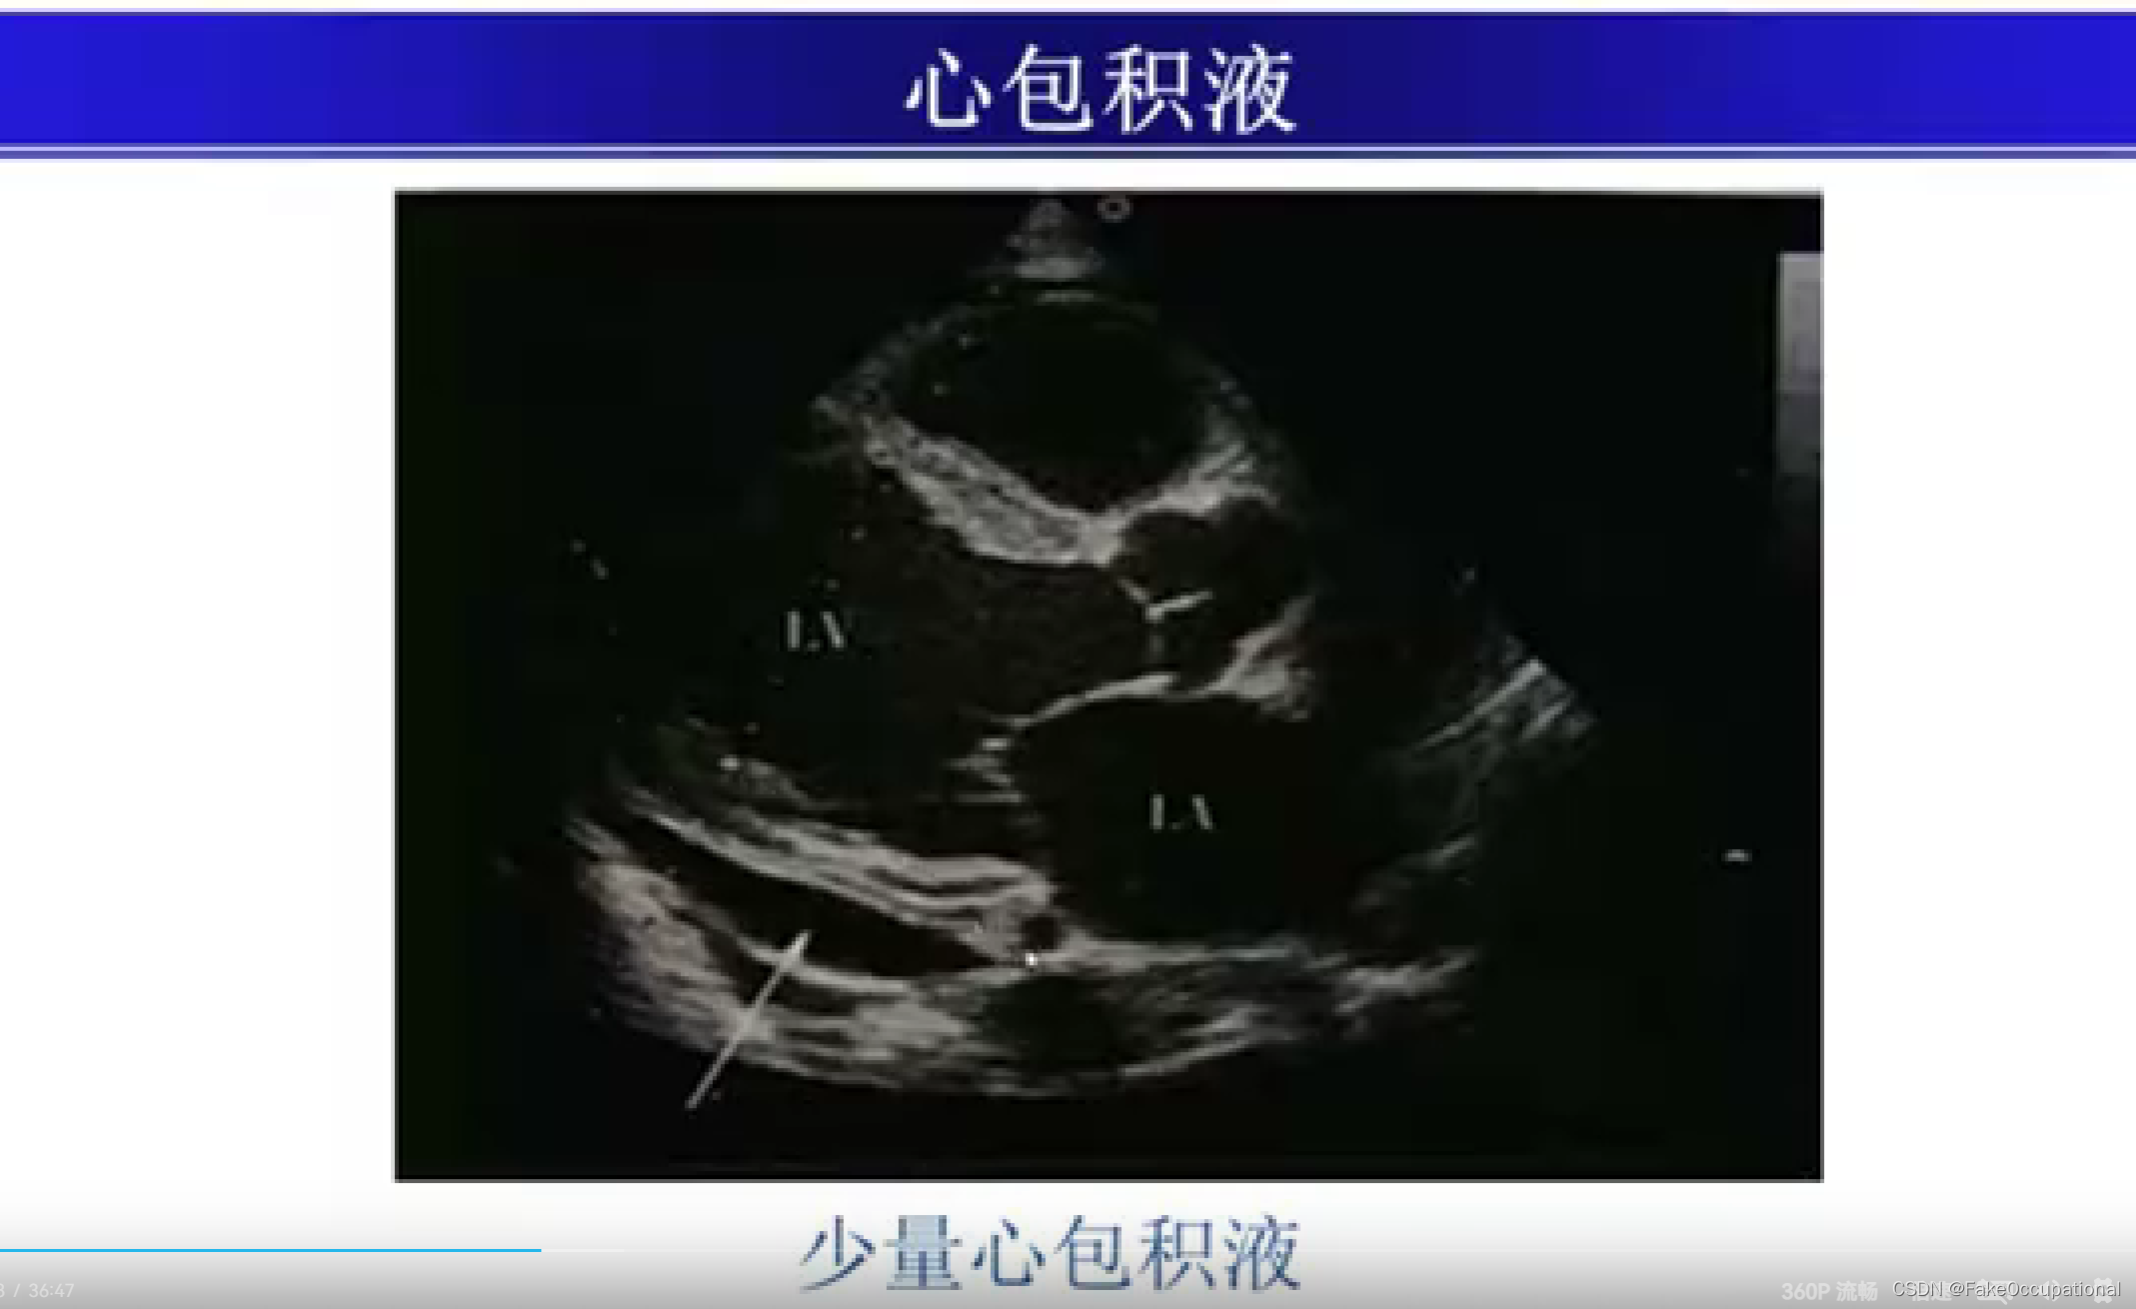

心包积液及心脏肿瘤

- 心包积液可出现于整个心包,也可局限于心包的局部,但心底部上方和心房后方很少发生液体积聚。心包积液时,心包腔可向内、外侧及心尖方向扩大。心包积液是心包炎最重要的表现之一,但心包炎并非必然出现心包积液。

心包积液超声定量

- 微量 (<50ml) : 左室后壁D2-3mm,右室前壁无液暗区;少量 (50-200ml) :左室后壁D10mm以内,右室前壁无或可疑液暗区;

- 中量 (200-500ml) : 左室后壁D10-20mm,右室前壁D5-10mm;

- 大量 (>500ml) :左室后壁D>20mm,右室前壁D>15mm,可出现心脏摆动征